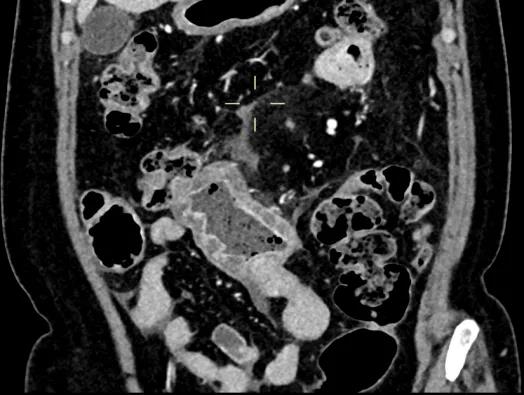

全腹增强CT扫描:克罗恩病并小肠穿孔、腹膜炎治疗后。中下腹部节段小肠肠壁增厚并周围渗出病变,较前进展,局部少量积液;局部小肠扩张并管壁水肿,可疑不全性肠梗阻;下腹壁切口疝形成。